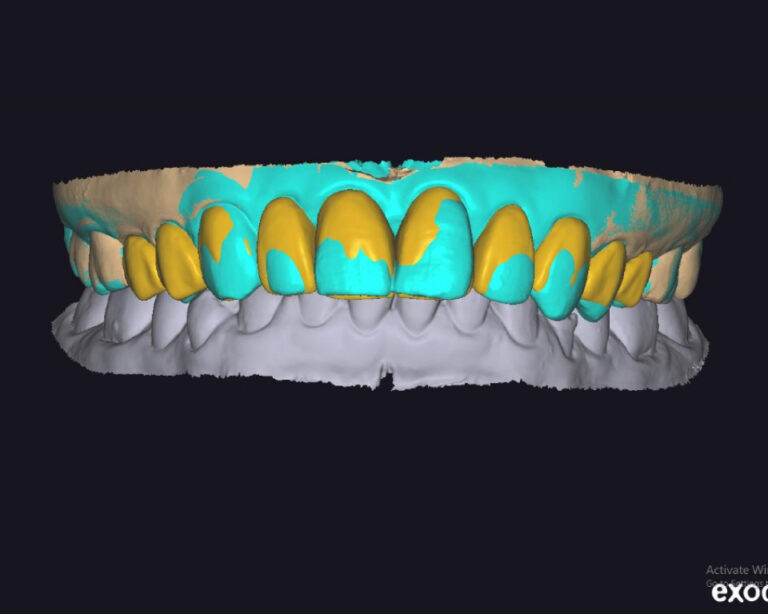

Case of the week